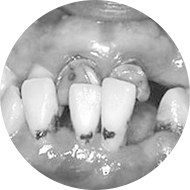

• 牙齿咬合紊乱

咬合紊乱:长期缺牙会导致局部咬合关系紊乱

• 牙周疾病

牙周疾病:牙周病、龋病的发生概率明显增加